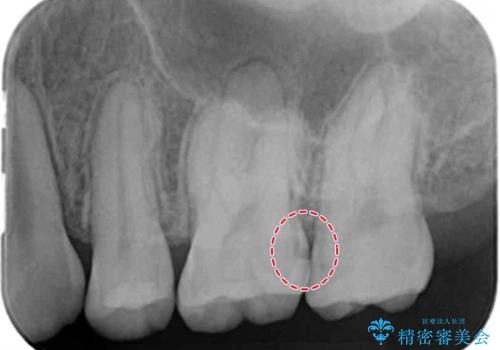

レントゲン画像上で歯と歯の間に虫歯が確認されました。

写真ではなかなか分かりづらいですが、歯と歯の間に虫歯があることがレントゲン画像から読み取ることができます。